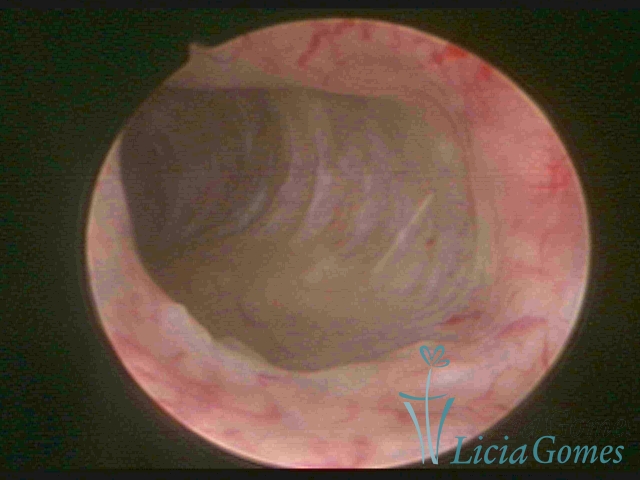

Bicornuate uterus

Malformation in which there is the lack of the flat portion of uterine fundus due to the lack of fusion on the proximal portion of paramesonephric ducts. The uterine fundus has two narrowed spaces in a divergent oblique angulation. It may be complete, from the fundus to the cervix; or partial, completely dividing the uterine cavity.

The tilted uterus which presents the most difficult hysteroscopic diagnosis occurs when there is only a small indentation of the uterine fundus.